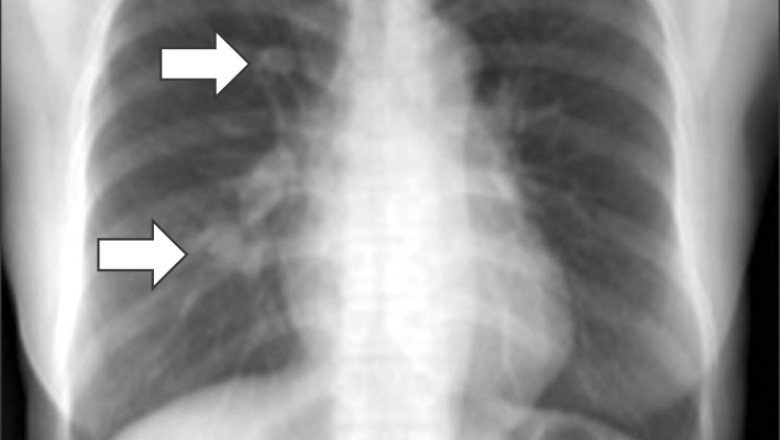

The exact cause of desmoid tumors is not fully understood, but they are thought to arise from abnormal growth of connective tissue cells called fibroblasts. Some Desmoid Tumors are associated with inherited genetic mutations, such as familial adenomatous polyposis (FAP), which is a rare genetic disorder that causes multiple polyps to form in the colon and rectum. In some cases, desmoid tumors can also be associated with trauma, previous surgery, or hormonal changes, such as during pregnancy.

Diagnosis of Desmoid Tumors can be challenging, as they often do not have specific symptoms or signs. They can be detected incidentally on imaging studies such as CT scans, MRIs, or ultrasound. Biopsy is often necessary to confirm the diagnosis and rule out other types of tumors.